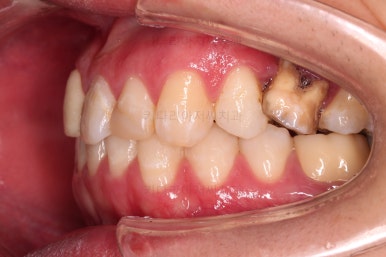

다행히 매복되었던 영구치는 잘 이동하였고요.

임플란트 자리도 적당한 크기로 점점 넓혀갑니다.

매복 영구치도 거의 다 배열되어 가고요.

임플란트 공간도 많이 확보되었습니다.

임플란트를 위한 기본 셋팅이 거의 완료되었습니다.

이 모습까지 13개월 걸렸네요.